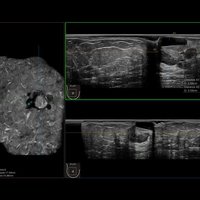

Das IBUS 60 ist ein intelligentes Brust-Vollvolumen-Ultraschallsystem der Marke SIUI.

Das IBUS 60 zeichnet sich durch Sicherheit und Komfort aus. Es bietet ein hochauflösendes Bild und reduziert somit Fehldiagnosen, was ideal für die Brustuntersuchung ist, insbesondere bei einer dichten Brust.

• Dreidimensionale Positionierung

• Nanopure Technologie zur Specklereduzierung